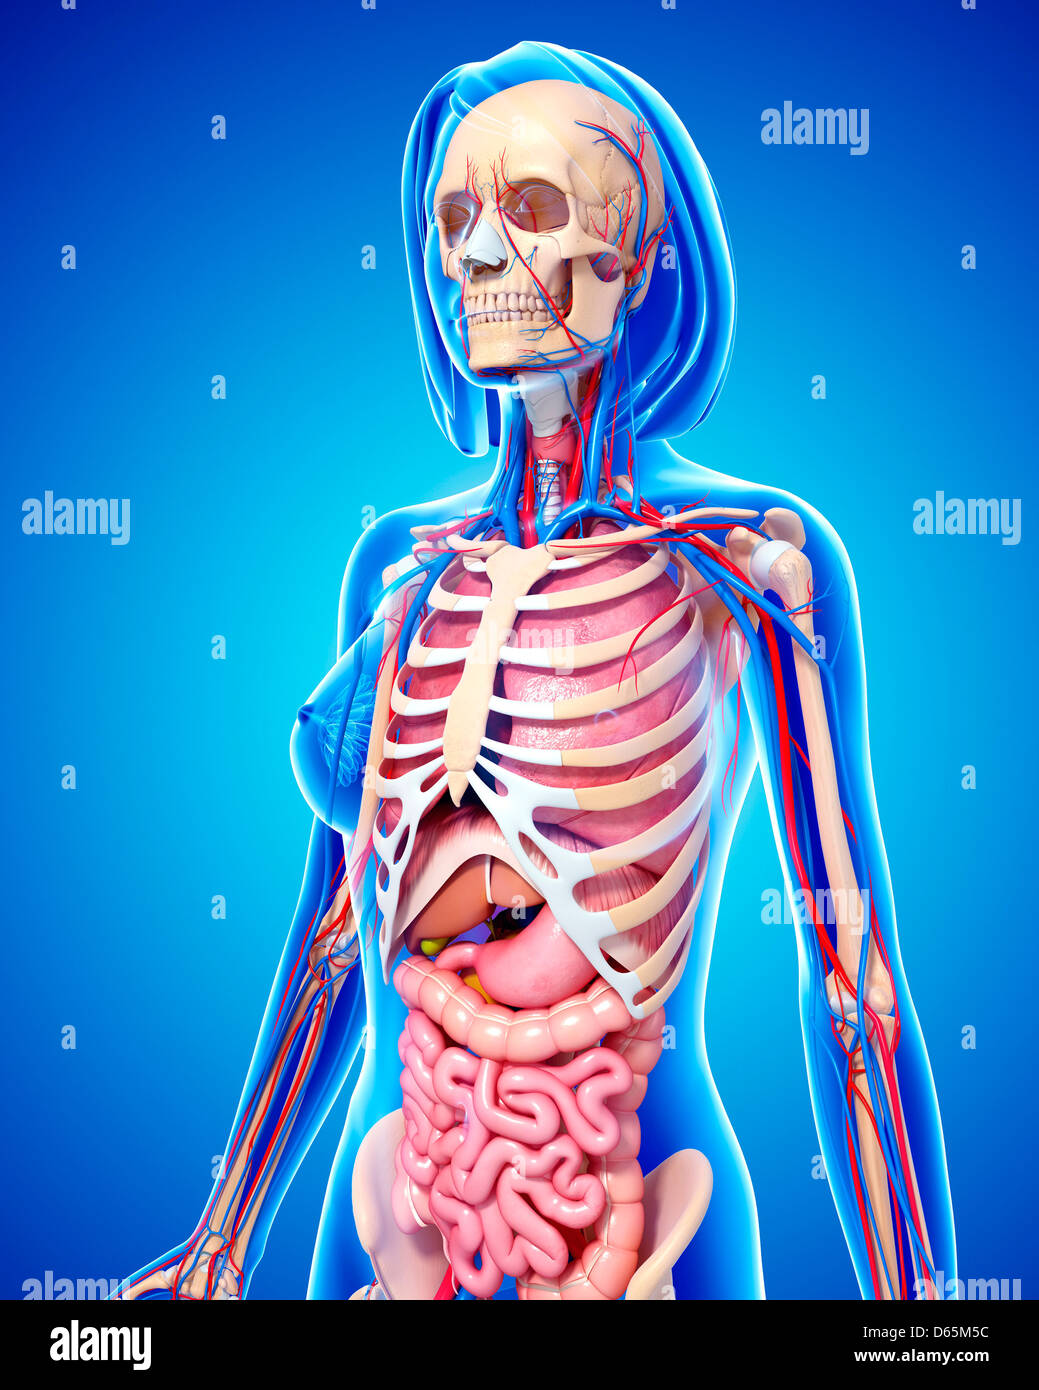

www.alamy.com3d Rendered Illustration Of The Female Anatomy Stock Photo - Alamy

www.alamy.com3d Rendered Illustration Of The Female Anatomy Stock Photo - Alamy

fineartamerica.com3d Rendered Illustration Of The Female Anatomy Stock Photo - Alamy

fineartamerica.com3d Rendered Illustration Of The Female Anatomy Stock Photo - Alamy